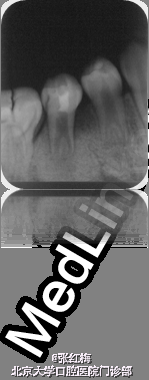

在牙髓再生术后1个月,3个月,5个月,9个月复查 1个月x线:45根尖周低密度影缩小,牙根继续发育。 3个月x线:45根尖周未见病变影,根周膜清晰,牙根继续发育。 5个月x线:45根尖周未见病变影,根周膜清晰,牙根继续发育。 9个月x线:45根尖周未见病变影,根周膜清晰,牙根继续发育,已近完成,髓腔缩小。 讨论:由于畸形中央尖一部分有髓角伸入,因此发现畸形中央尖应根据不同情况给予及时或相应处理。对于圆钝而无妨碍的中央尖可以不做处理。尖而长的中央尖容易折断或被磨损而露髓.可在麻醉和严格消毒下将此尖一次磨除。制备洞形,盖髓充填。还有一种方法树脂在牙尖周围加固防折,使畸形尖随牙齿一同发生生理磨耗,促使髓角形成修复性牙本质,可用于尚未建合的牙。短期内折断的畸形中央尖无牙髓根尖炎症状,且牙髓活力正常者,备洞盖髓充填。折断的畸形中央尖有牙髓炎根尖炎者,往往牙根未发育完成,需做根尖诱导形成术,或牙髓再生治疗。 牙髓坏死或者根尖炎年轻恒牙的牙髓治疗方法有:根尖诱导成形术,MTA根尖封闭技术,近年来的牙髓再生技术。 根尖诱导成形术,所用根管内充填材料是氢氧化钙及其制剂,诱导根尖周的组织在根尖部形成钙化屏障。需要多次复诊和更换根充药物,疗程较长,增加了根管再次污染的可能性,并不是所有都能形成根尖部的钙化封闭。而且根管壁仍然薄弱,增加了远期根折的风险。 MTA具有良好的生物相容性和封闭性,MTA根尖封闭技术中用其特性封闭根尖,防止充填材料在根尖部的外溢。生物相容性好,可以诱导矿化,但其完全固化需要较长时间,不易操作,抗菌效果不确定,价格昂贵。 牙髓血管再生术通过在操作中彻底有效的根管消毒,尽量保护牙髓干细胞和牙乳头间充质干细胞,并为这些干细胞的增殖和分化提供良好的环境,这些干细胞在信号分子和盖髓剂矿物三氧化物凝聚体(mineral trioxide aggregate,MTA)的诱导下,可以分化为成牙本质细胞和成牙骨质细胞等,从而在牙根继续发育中发挥着重要作用。研究表明,在坏死感染的年轻恒牙根管内进行成功的血管再生后,其根尖周炎症能愈合且牙根得以持续发育,出现根尖闭合、根管长度增加及管壁增厚等,牙髓血管再生术有可能成为治疗年轻恒牙根尖周炎的新选择。